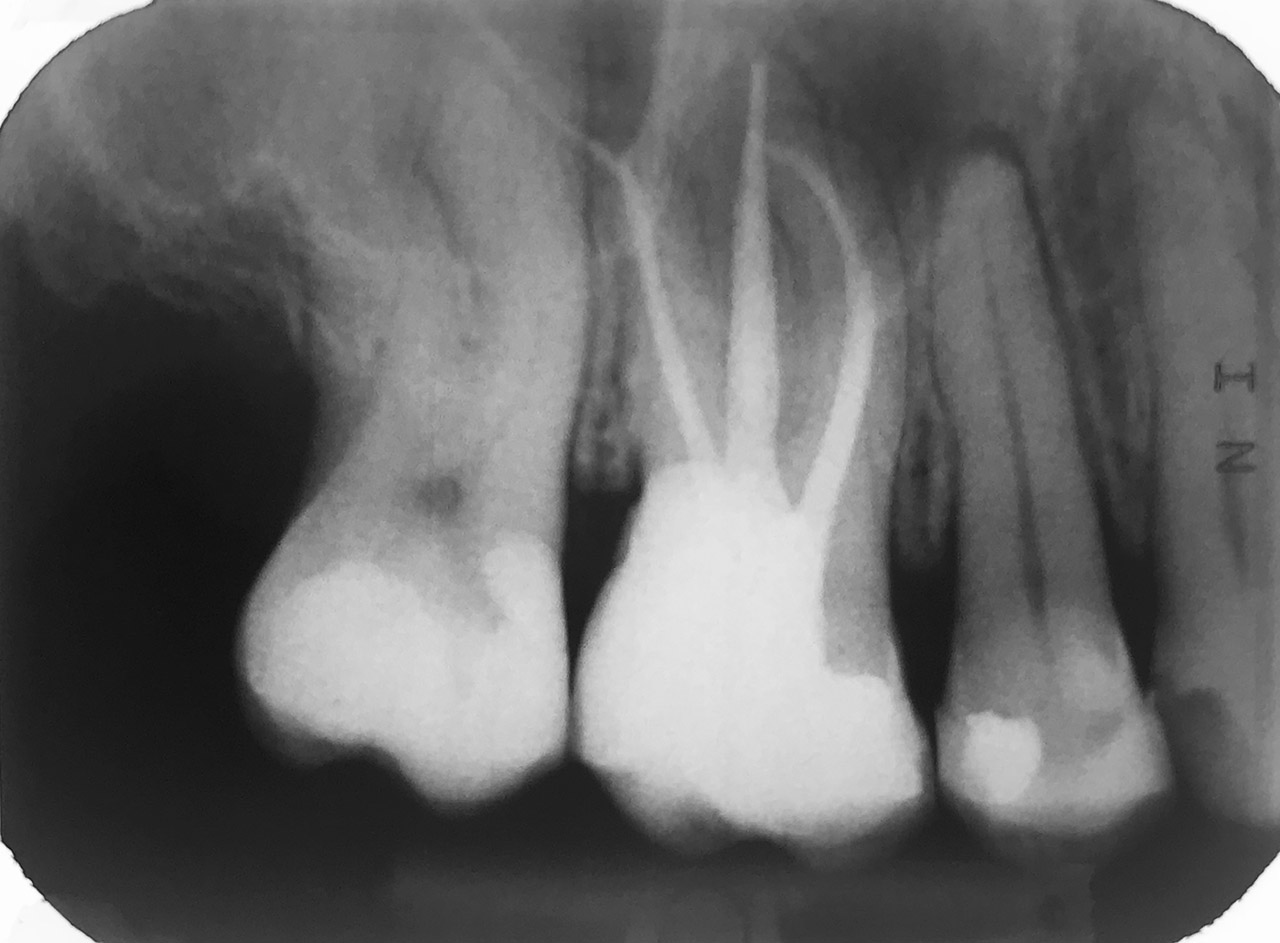

Wurzelbehandlung/Endodontie:

Massiver Paro-/Endodefekt bei den Zähnen 38&37. Extraktion von 38 (Weisheitszahn) und Wurzelbehandlung von 37 (4 Kanäle). Defekt vollständig ausgeheilt.